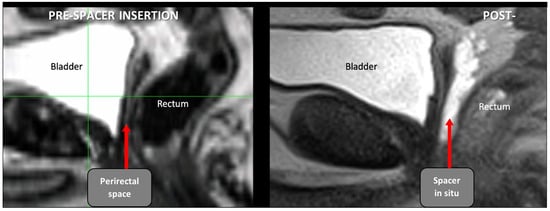

2.3. Radiation Therapy

A total of 39 patients had a pre-spacer computerized tomography (CT) scans available for assessment. These are not routine but conducted as planning CT scans prior to a patient-led decision change regarding rectal spacer insertion. Pre- (when available) and post-perirectal spacer CT planning scans, together with post-perirectal spacer MRI scans, were acquired for dosimetric comparison (see Figure 3). The prostate bed CTV was delineated according to standard Australian guidelines [11], and the CTV was uniformly expanded by 7 mm [12] to create the planning target volume (PTV). The prescribed dose to the prostate bed was 70.2 Gy in 1.8 Gy fractions using volumetric arc radiation therapy [12]. Given PSMA-PET scans were negative in these patients, pelvic lymph nodes were not included in the radiation. The PTV and rectal dosimetry for the two sets of CT planning scans (PTV 7 mm/pre spacer and PTV 7 mm/post spacer) were compared.

Figure 3.

Comparison of planned radiation area (green line) in the same patient pre- and post-rectal spacer insertion. Prior to spacer insertion, a long length of rectal wall (delineated by dotted orange line) was exposed to high dose radiation. This decreased by the use of hyaluronic acid spacer (yellow line). Abbreviations: CTV—clinical tumour volume, PTV—planning tumour volume, VUA—vesicoureteric anastomosis.